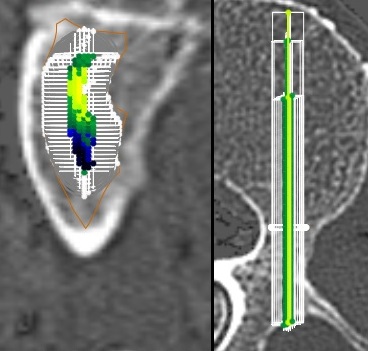

FAQ: How FMax-G deals with the key issue of screw insertion precision ?

Precision for screw insertion is a key issue whether the technique is free-hand or navigated. There are many possible insertion trajectories. As a result, each theoretical trajectory does not have the same strength since the bone density varies within the pedicle and anterior body.

PedicleForce simulates all relevant breachless trajectories with the full range of your vendor screw set in diameter and length and predict each resulting anchorage.

Then PedicleForce selects the unmissable result for breachless trajectories: the baseline guaranteed construct prediction for each possible screw size of the whole screw range given the actual screw will be inserted breachless.

The new paradigm: FMax-G = the baseline FMax you can rely on for planning independly from the insertion technology precision.

FMax-G: baseline anchorage prediction with ρ=.99

PedicleForce has be confirmed by the in vitro golden standard testing: a 45 cadaveric vertebrae screw pullout with an accuracy of ρ = .99